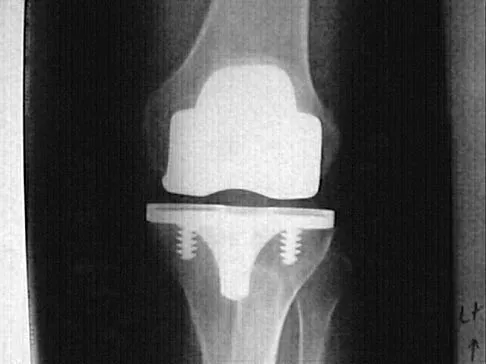

Question 20

Osteolysis after total knee arthroplasty can be minimized through prosthetic design features such as

Explanation